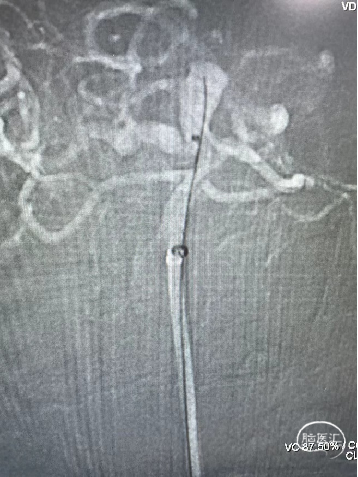

术中操作-预置支架导管+填圈:

预置支架导管

置入弹簧圈微导管

置入弹簧圈

填圈后通过微导管并释放支架

导丝通过&支架导管到位

释放支架:

支架到位

头端打开

中间打开

近端打开,后予以支架导管通过支架将其充分打开。

术后即刻复查:远端血管通畅、支架打开良好。

术后正位复查